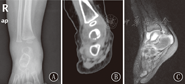

注:A:X线显示距骨骨质密度不均匀降低,踝关节周围软组织肿胀;B:MRI显示左距骨内可见斑片状异常混杂信号影,以长T1长T2信号为主,周围软组织肿胀 A:X-ray showed that there was an uneven decline of bone mineral density in talus bone,and peripheral soft tissue of right ankle was swelling;B:MRI showed patchy mixed signal with the intense T1 and T2 signal as primary key in talus bone and soft tissue masses around the lesion